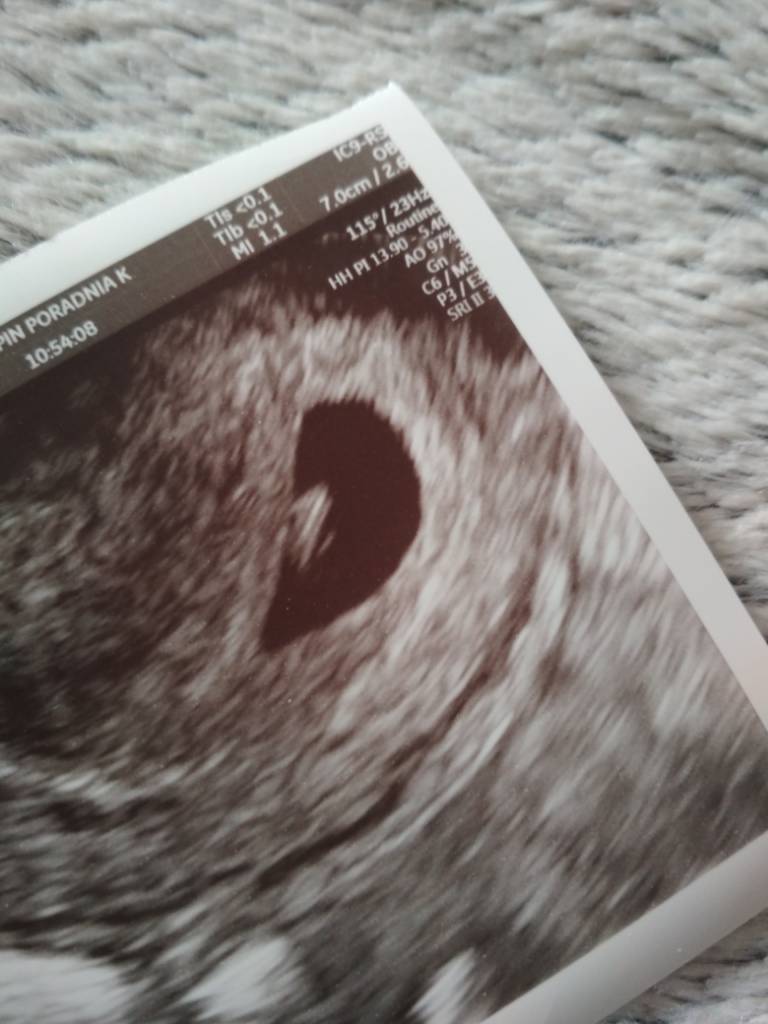

Jesteśmy już po :) serduszko biło pięknie [emoji3590] usg trochę zamazane ale na usg było pięknie widac jak serduszko bije :) termin na 6 listopada :) przeszczesliwa jestem i w końcu spokojna :)

Powiedzcie mi te 7.0cm/2.6 to co to za wymiary? Pecherzyk i zarodek? Bo nie dopytalam lekarza z tego wszystkiego :)

Dziękuję za trzymanie kciukow :* Zobacz załącznik 953007